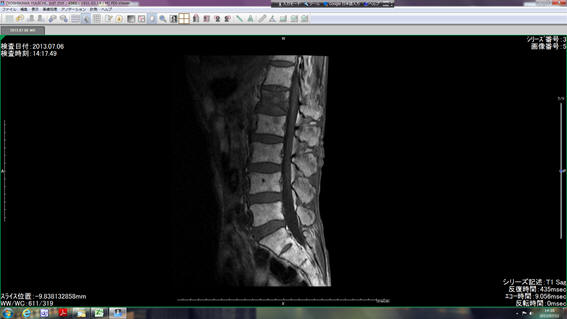

すぐ翌6日に近くの中央総合病院でMRI検査をやってもらいました。そして、8日に、その検査結果の写真やDVDをもって整形外科医院で原因を調べてもらいました。急性腰痛症で、「筋筋膜性腰痛症」といっても、これは状態の表現で、病因ではなく、原因にはいろいろあるようです。

をMRI検査の詳しいデータで診てもらった結果、第一腰椎の骨が骨折しており、それによって痛みが出ていることが解ったそうです。(右の腰椎のMRI写真の上から3つ目の黒っぽく見える部分が骨折しているところだそうです。)

つまり1〜2週間で終わるいわゆる「ぎっくり腰」などではない骨折だとのことです。普通は、腕や脚の骨折の場合と同じように、コルセットやギプスなどを腰の周りに強く当てて、あとは痛み抑えの薬などの服用し、短くとも2〜3ヵ月ぐらいがかかる治療が